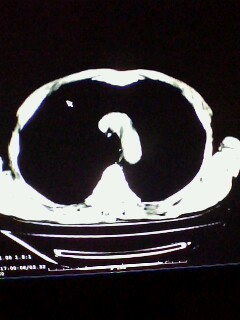

标题: CT28315:咳嗽咳痰咯血半月并胸痛 [打印本页]

标题: CT28315:咳嗽咳痰咯血半月并胸痛

1、纵膈窗效果不好,初步考虑左肺下叶感染性病灶,建议正规抗炎治疗后复查   2、右肺下叶陈旧性病灶伴局部胸膜增厚。